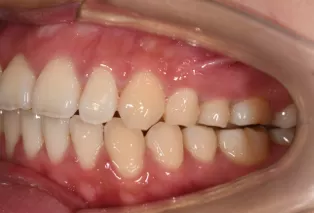

Intraoral photos